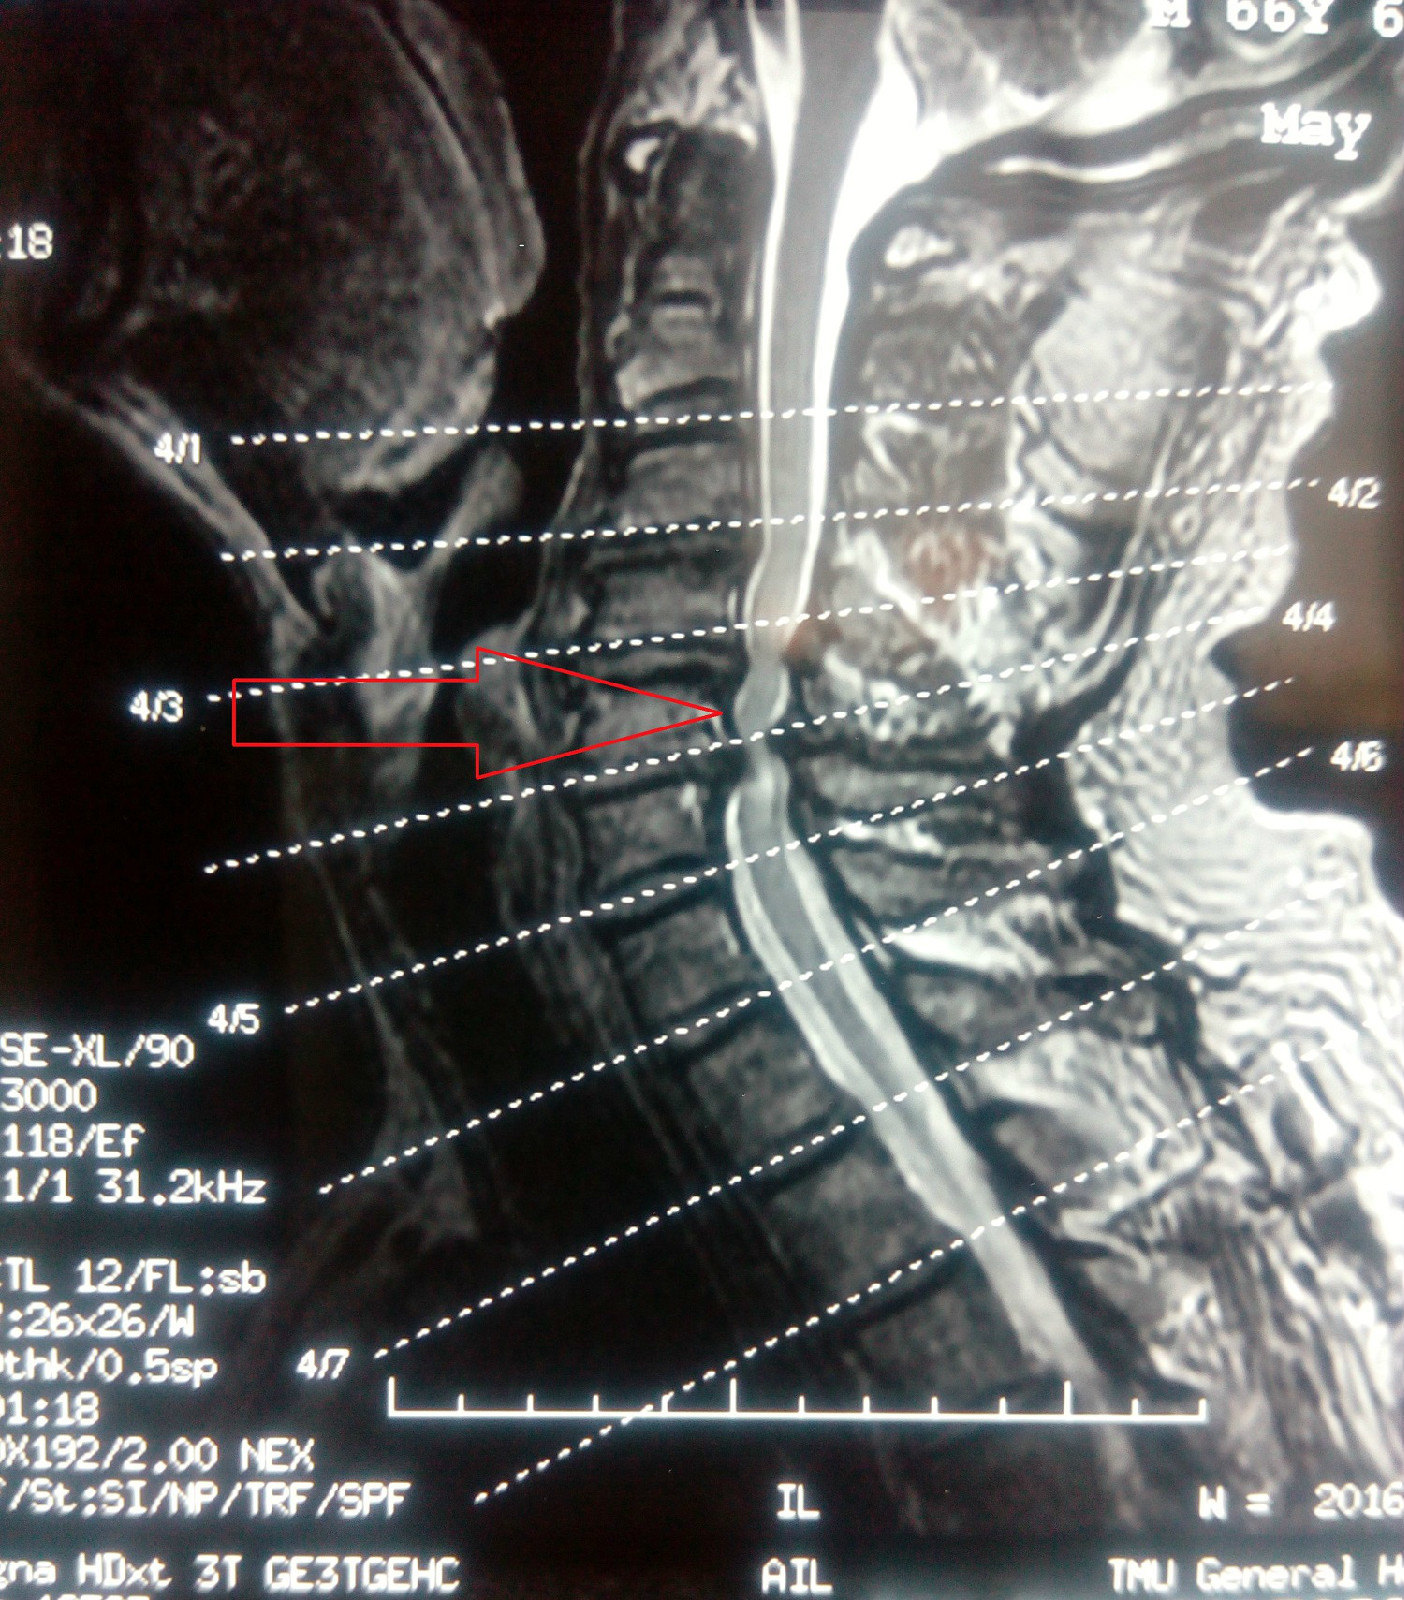

入院后查颈椎mri示:椎间盘膨出,约平颈6以下颈胸髓内异常,考虑中央导

我的门诊病历: 惨痛教训,颈椎病按摩后导致不全瘫痪,小便失禁